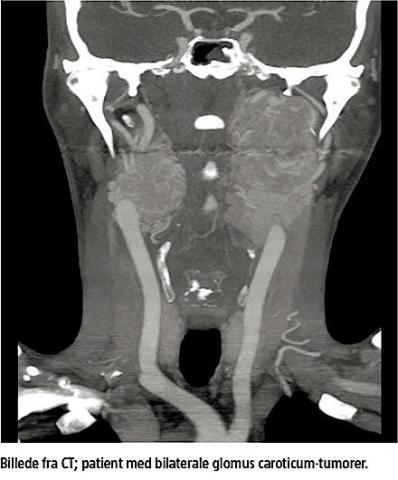

HHPGL navngives efter lokalisation. Glomus caroticum-tumorer udgår fra autonome ganglier ved carotisbifurkaturen, glomus jugulare-tumorer fra celler ved bulbus venae jugularis, glomus tympanicum-

tumorer fra celler i plexus tympanicus og vagusparagangliomer typisk fra det inferiore vagusganglion. Omkring 80% af HHPGL er glomus caroticum-tumorer eller glomus jugulare-tumorer [4, 5]. Ca. en tredjedel af alle glomus jugulare-tumorer breder sig til det intrakraniale rum [4, 9-11].